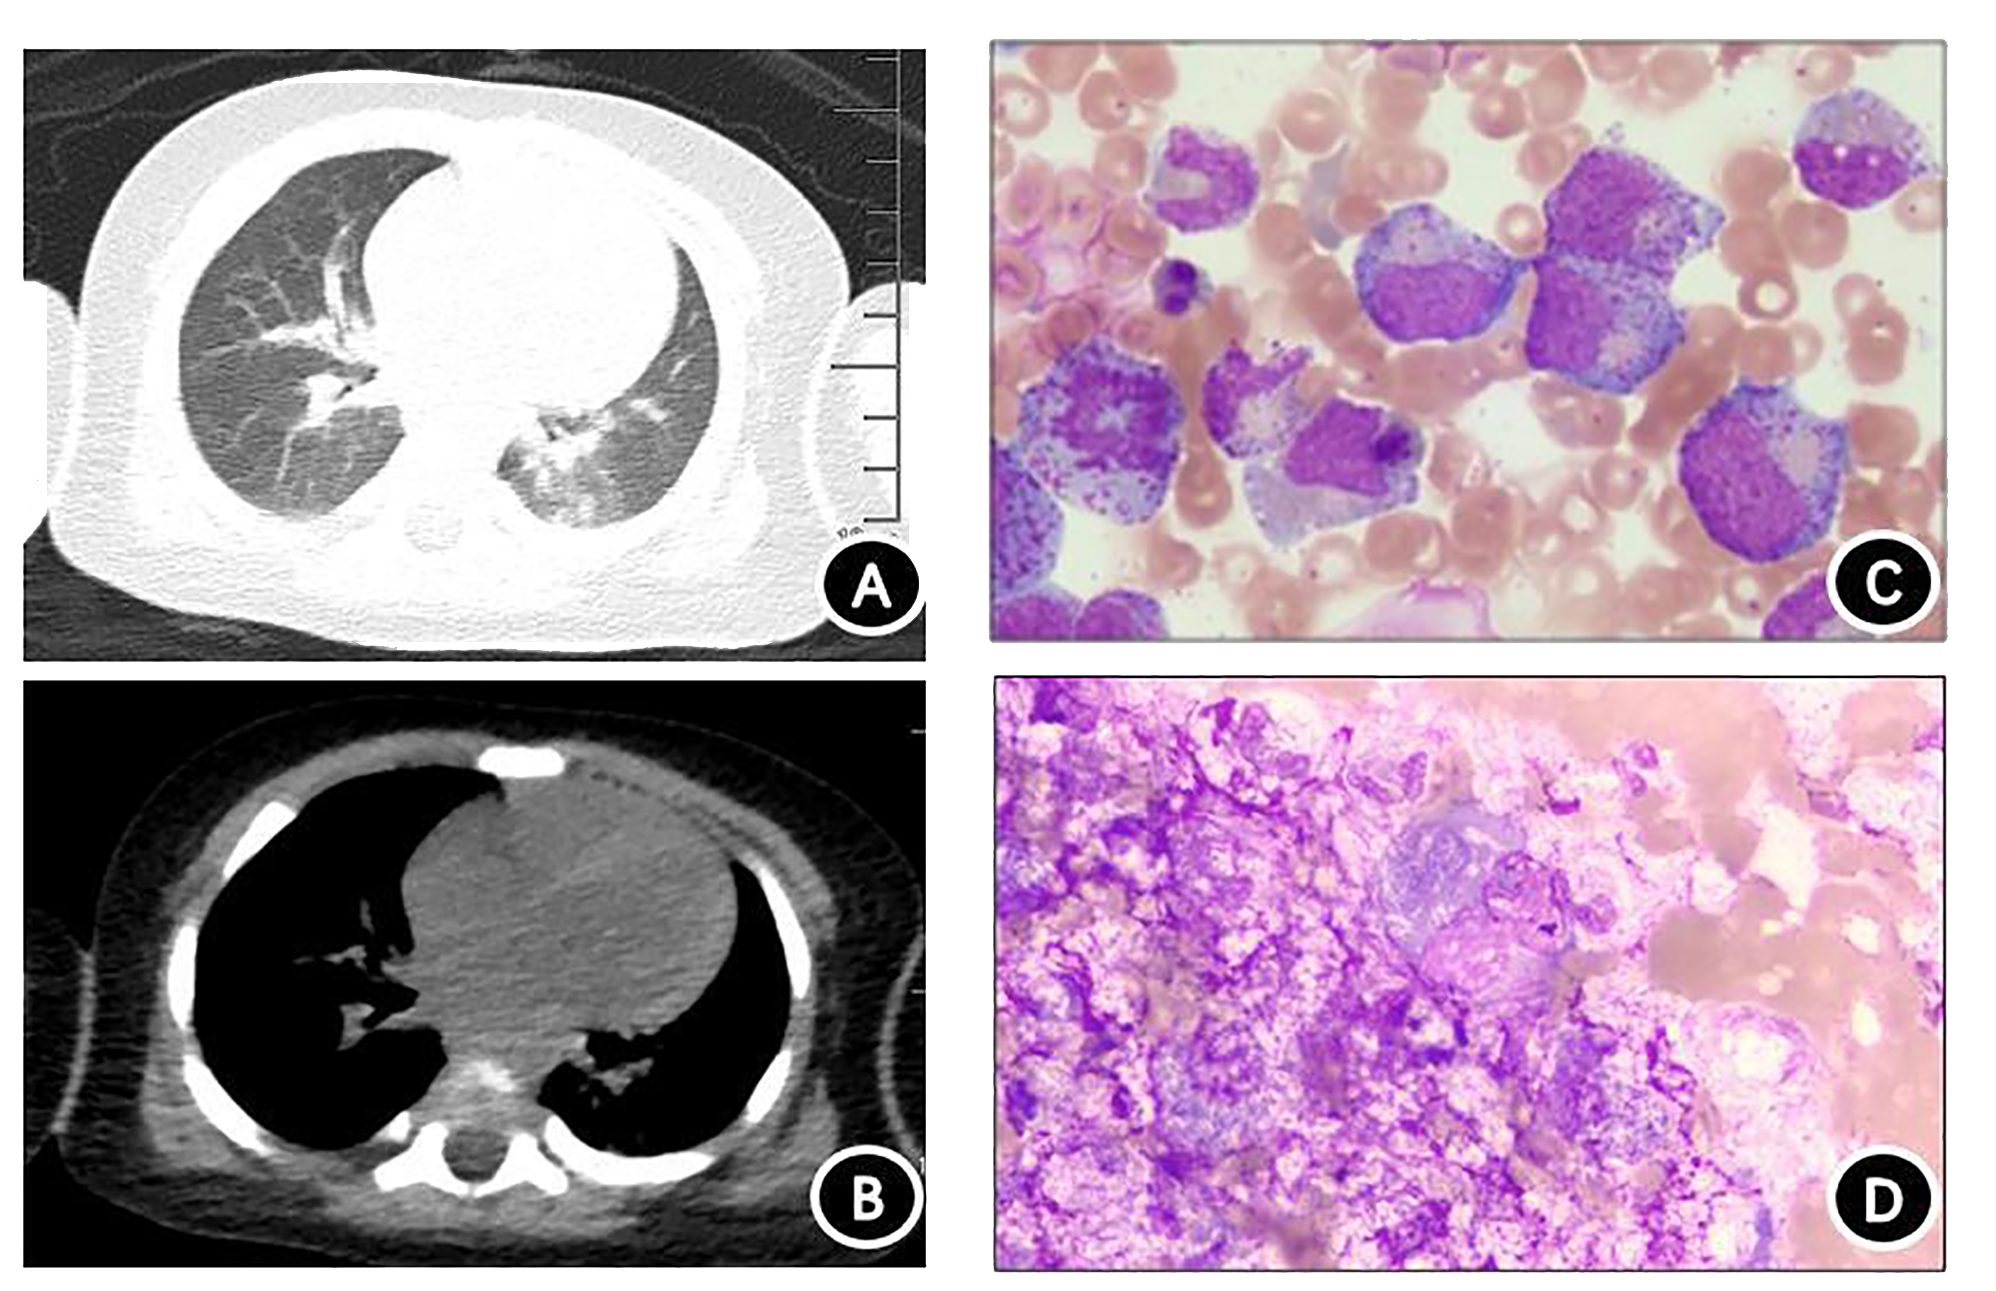

Chest computed tomography (CT) revealed slight inflammation in both lungs (Figures 2A, B). Abdominal CT indicated liver and spleen enlargement with some fluid accumulation in the abdominal and pelvic cavities. Bone marrow examination revealed active hyperplasia of bone marrow, neutrophils with toxic granulation and vacuoles, iron-deficient erythroid cells, and poor platelet production in megakaryocytes (Figure 2C). Langerhans cells were found on the skin print (Figure 2D) and the bovine M. tuberculosis complex was detected in the blood using metagenomic next-generation sequencing (mNGS) technology.

Figure 2

www.frontiersin.org

Figure 2 Chest computed tomography (CT) and cytological examination. (A) Chest CT lung window. (B) Chest CT mediastinal window showing scattered inflammation in both lungs. (C) Bone marrow specimen demonstrating significant proliferation and activation of bone marrow, with toxic particles and vacuolar degeneration visible in granulocytes. Red blood cells are mainly composed of middle- and late-stage erythrocytes, and no plate-producing megakaryocytes are present. (D) Rash imprint showing approximately 18% of suspected Langerhans tissue cells, with abundant cytoplasm filled with small grayish-purple particles. The nucleoli are circular or irregular in shape, and the cytoplasm is thick and loose.